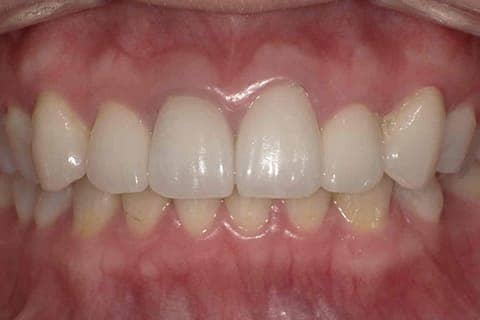

健康に美しく臨床実績集

虫歯や歯周病、事故などでの欠損、

噛めるようになりたい、見た目の美しさの追求など、

審美的に機能的に回復した治療経過報告症例です。